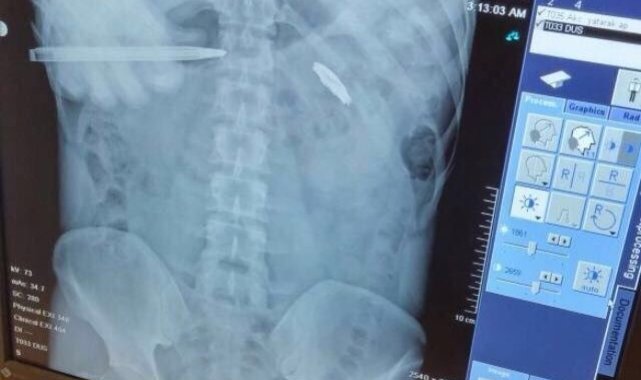

15 Temmuz darbe girişimi esnasında demokrasiye sahip çıkmak için sokağa çıkan Musa İlhan, hainlerin sıktığı kurşunla kalbinin 2 milimetre altından yaralandı. Kurşunun vücudundan çıkarılmasının riskli olması nedeniyle 8 yıldır mermiyle yaşayan İlhan, "9 yıldır göğsümde gaziliğin nişanesini taşıyorum. Müslüman Türk milleti için gazilik nişan ise şehitlik düğündür. Çoğu zaman hayıflanıyorum keşke şehit olabilseydim diye. Cumhurbaşkanımız, Cumhur İttifakımız büyük bir özveriyle risk aldı. 'Terörsüz Türkiye' inşallah başarılı olur. Bir ulus için, bir devlet için ayağındaki en büyük pranga terördür. Terörden kurtulan her ülke şahlanmıştır. İnşallah Türkiye Yüzyılı'nda terörden kurtulmuş ve şahlanmış Türkiye'yi bizlere görmek nasip olur. Büyük Türkiye'nin ayak seslerini bütün dünya hissediyor" dedi.Fetullahçı Terör Örgütü'nün (FETÖ) 15 Temmuz 2016 tarihinde gerçekleştirdiği hain darbe girişiminin üzerinden 9 yıl geçti. Darbe girişiminde her yaştan vatandaş sokağa çıkarak darbeye 'dur' dedi. O vatandaşlardan kimi şehit oldu kimi de yaralanarak gazilik mertebesine erişti. Demokrasiye sahip çıkmak için sokağa çıkan Musa İlhan da darbeye karşı duranlardandı. İlhan, trafikte seyir halindeyken 15 Temmuz hain darbe girişimini radyodan öğrendi. Vatan savunması için sokakta kalan Musa İlhan, korkusuz bir şekilde darbeci askerlerin karşısına dikildi. Darbecilerin kurşunlarının hedefi olan İlhan, kalbinin 2 milimetre altına isabet eden mermiyle yere yığıldı. Ağır yaralanan İlhan, çevredekiler tarafından hastaneye kaldırıldı. 4 gün yoğun bakımda kalan İlhan, 2 ay süren tedavinin ardından sağlığına kavuştu. Ancak cerrahi müdahale riskli olduğu için kurşun çıkarılamazken, 9 yıldır hainlerin sıktığı mermiyle yaşıyor."Bir ulus için, bir devlet için ayağındaki en büyük pranga terördür"Terörsüz Türkiye hakkında konuşan Gazi Musa İlhan, "Afet Koordinasyon Merkezi'nde vuruldum. Tabii 9 yıl oldu, anılarımız bazen depreşiyor. Oradan geçerken, vurulduğum yeri görüyorum. Ateş eden askerin durduğu yeri hayal ediyorum. Zor bir süreç. 9 yıldır göğsümde gaziliğin nişanesini taşıyorum. Müslüman Türk milleti için gazilik nişan ise şehitlik düğündür. Çoğu zaman hayıflanıyorum keşke şehit olabilseydim diye. Rabbim tekrar yaşatmasın. Güncel Türkiye'de gördüğümüz Cumhurbaşkanımız, Cumhur İttifakımız büyük bir özveriyle risk aldı. 'Terörsüz Türkiye' inşallah başarılı olur. DEAŞ'ı, FETÖ'sü, DHKP-C'si vesaire bütün terör örgütlerinin tamamından kurtulmuş oluruz. Bir ulus için, bir devlet için ayağındaki en büyük pranga terördür. Terörden kurtulan her ülke şahlanmıştır. İnşallah Türkiye Yüzyılı'nda terörden kurtulmuş ve şahlanmış Türkiye'yi bizlere görmek nasip olur. Ümitliyiz, umutluyuz. Büyük Türkiye'nin ayak seslerini bütün dünya hissediyor. Şu anki başarılarımızı bazıları perdelemek isteseler de emin olun çok büyük başarılarımız var. Özellikle savunma sanayinde. Cumhurbaşkanımızın 'dünya 5'ten büyüktür' diyerek haykırışının çoğu ülkeler bilincine vardı. Cumhurbaşkanımızın yanında ve arkasında saf tutmaya başladılar" ifadelerini kullandı."Çıplak ellerle nasıl tankların durdurulduğunu tüm dünya görmüştür"15 Temmuz hain darbe girişiminde halkın iradesini tüm dünyanın gördüğünü belirten Musa İlhan, "Sanki 15 Temmuz'u unutturmaya, önemsizleştirmeye çalışılır gibi bir ibare var. Belki bizler görmeyeceğiz ama eminiz ki ileride 15 Temmuz'un ne kadar değerli ve vahim bir durum olduğunu, ülkemizin bekasına kastedilmiş bir darbe, işgal girişimi olduğunu anlayacaklar. O zamanda Cumhurbaşkanımız kıymeti, değeri anlaşılacak. Rabbim uzun ömürler versin. Israrla, her konuşmasında 15 Temmuz'dan, halkın iradesinden bahsediyor. Onun dışında kimse Türkiye Cumhuriyeti'ndeki kimse kolay kolay sokaklara çıkmaz. Mesele vatansa sokağa çıkılır. Mesele bayraksa sokağa çıkılır. Çıkıldığında da çıplak ellerle nasıl tankların durdurulduğunu tüm dünya görmüştür. Geçen günlerde, Cumhurbaşkanımızın Amerika Başkanı Trump ile bir muhhabetini okudum. Trump, NATO'daki toplantıda kaç askerimizin olduğunu soruyor. Cumhurbaşkanımız ise 550 ya da 600 bin askerimizin olduğunu söylüyor. Trump, 'senin askerin 86 milyon' diye cevap veriyor. O zamanlar Amerika Başkanı değildi. 'Televizyon ve internetten gördüğümde 86 milyonun sokaktaydı' diyor. Bunu bütün dünya görüyor. Bizim 86 milyon asker olduğumuzu, konu vatan olduğunda 86 milyonun nasıl sokağa çıkacağını Amerika Başkanı bile gördüğüne göre Allah'ın izniyle sırtımız yere gelmez" diye konuştu."Mesele vatansa gerisi teferruattır"15 Temmuz hain darbe girişimi gecesini tekrar yaşayarak anlatan Musa İlhan, "AKOM'dan sonra niyetim Boğaz Köprüsü'ne geçmekti. AKOM'a girer girmez ateş edildi. Önce tabii biraz korkar gibi olduk. Lojistik Destek Merkezi'nde böyle bir şey yaşamadık. Oradaki askerlerin kimi ılımlıydı, çıkardık. Hatta arkalarından tezahürat yaptık. 'En büyük asker, bizim asker' diye. Aynı ruh haliyle gittiğimiz için AKOM'a da böyle bir şey beklemiyorduk. Gideceğiz, oradaki askerle konuşacağız, ikna edeceğiz, belki içerisinde birkaç tane taşkınlık yapan olacak çünkü Lojistik Destek Merkezi'nde öyle olmuştu. Ateş açılacağı hiç aklımızın ucuna gelmemişti. Zaten kaçar gibi olduk. Sonrasında tekrar gittim. Devamını hatırlamıyorum. 'Burası bizim işyerimiz, burası bizim toprağımız, sen askersin senin yerin kışla' diye bağırıyormuşum. Yanımdaki hocam ve arkadaşlarım, 'vuracaksan vur' diye yürüdüğümü söylüyor. 2 dakika sonra vurulmuşum zaten. Gerisini hatırlamıyorum zaten, yoğun bakım. İlk uyandığımda hemşire hanıma Cumhurbaşkanımızın yaşayıp yaşamadığını sordum. Hemşire hanım, 'Cumhurbaşkanı yaşıyor, sen kendine bak, şu an da televizyonda konuşuyor' demişti. Mesele vatansa gerisi teferruattır. Gazilik bir Müslüman için nişandır. Allah herkese nasip etsin. Şu yarım, engelli halimle 21 yaşında bir kızım var, nasip olursa 3 ay sonra bir kızımız daha olacak, o kızımı ben kundakta bırakırım yine koşa koşa şehit olmak için giderim" şeklinde konuştu.